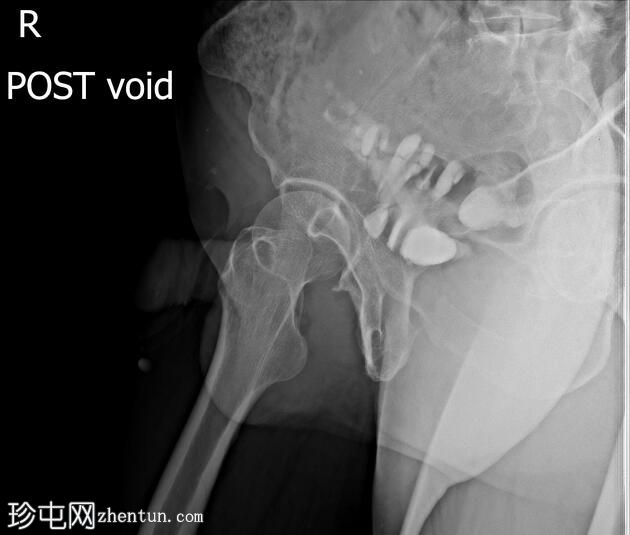

排尿困难。既往有膀胱癌病史及根治性膀胱切除术。

前列腺部、膜部、球部及阴茎部尿道均正常。

造影剂经尿道注入,开始充盈具有肠袢特征的新膀胱。

该患者确诊为移行细胞癌后行膀胱切除术。治疗方案包括根治性膀胱切除术及新膀胱重建术。